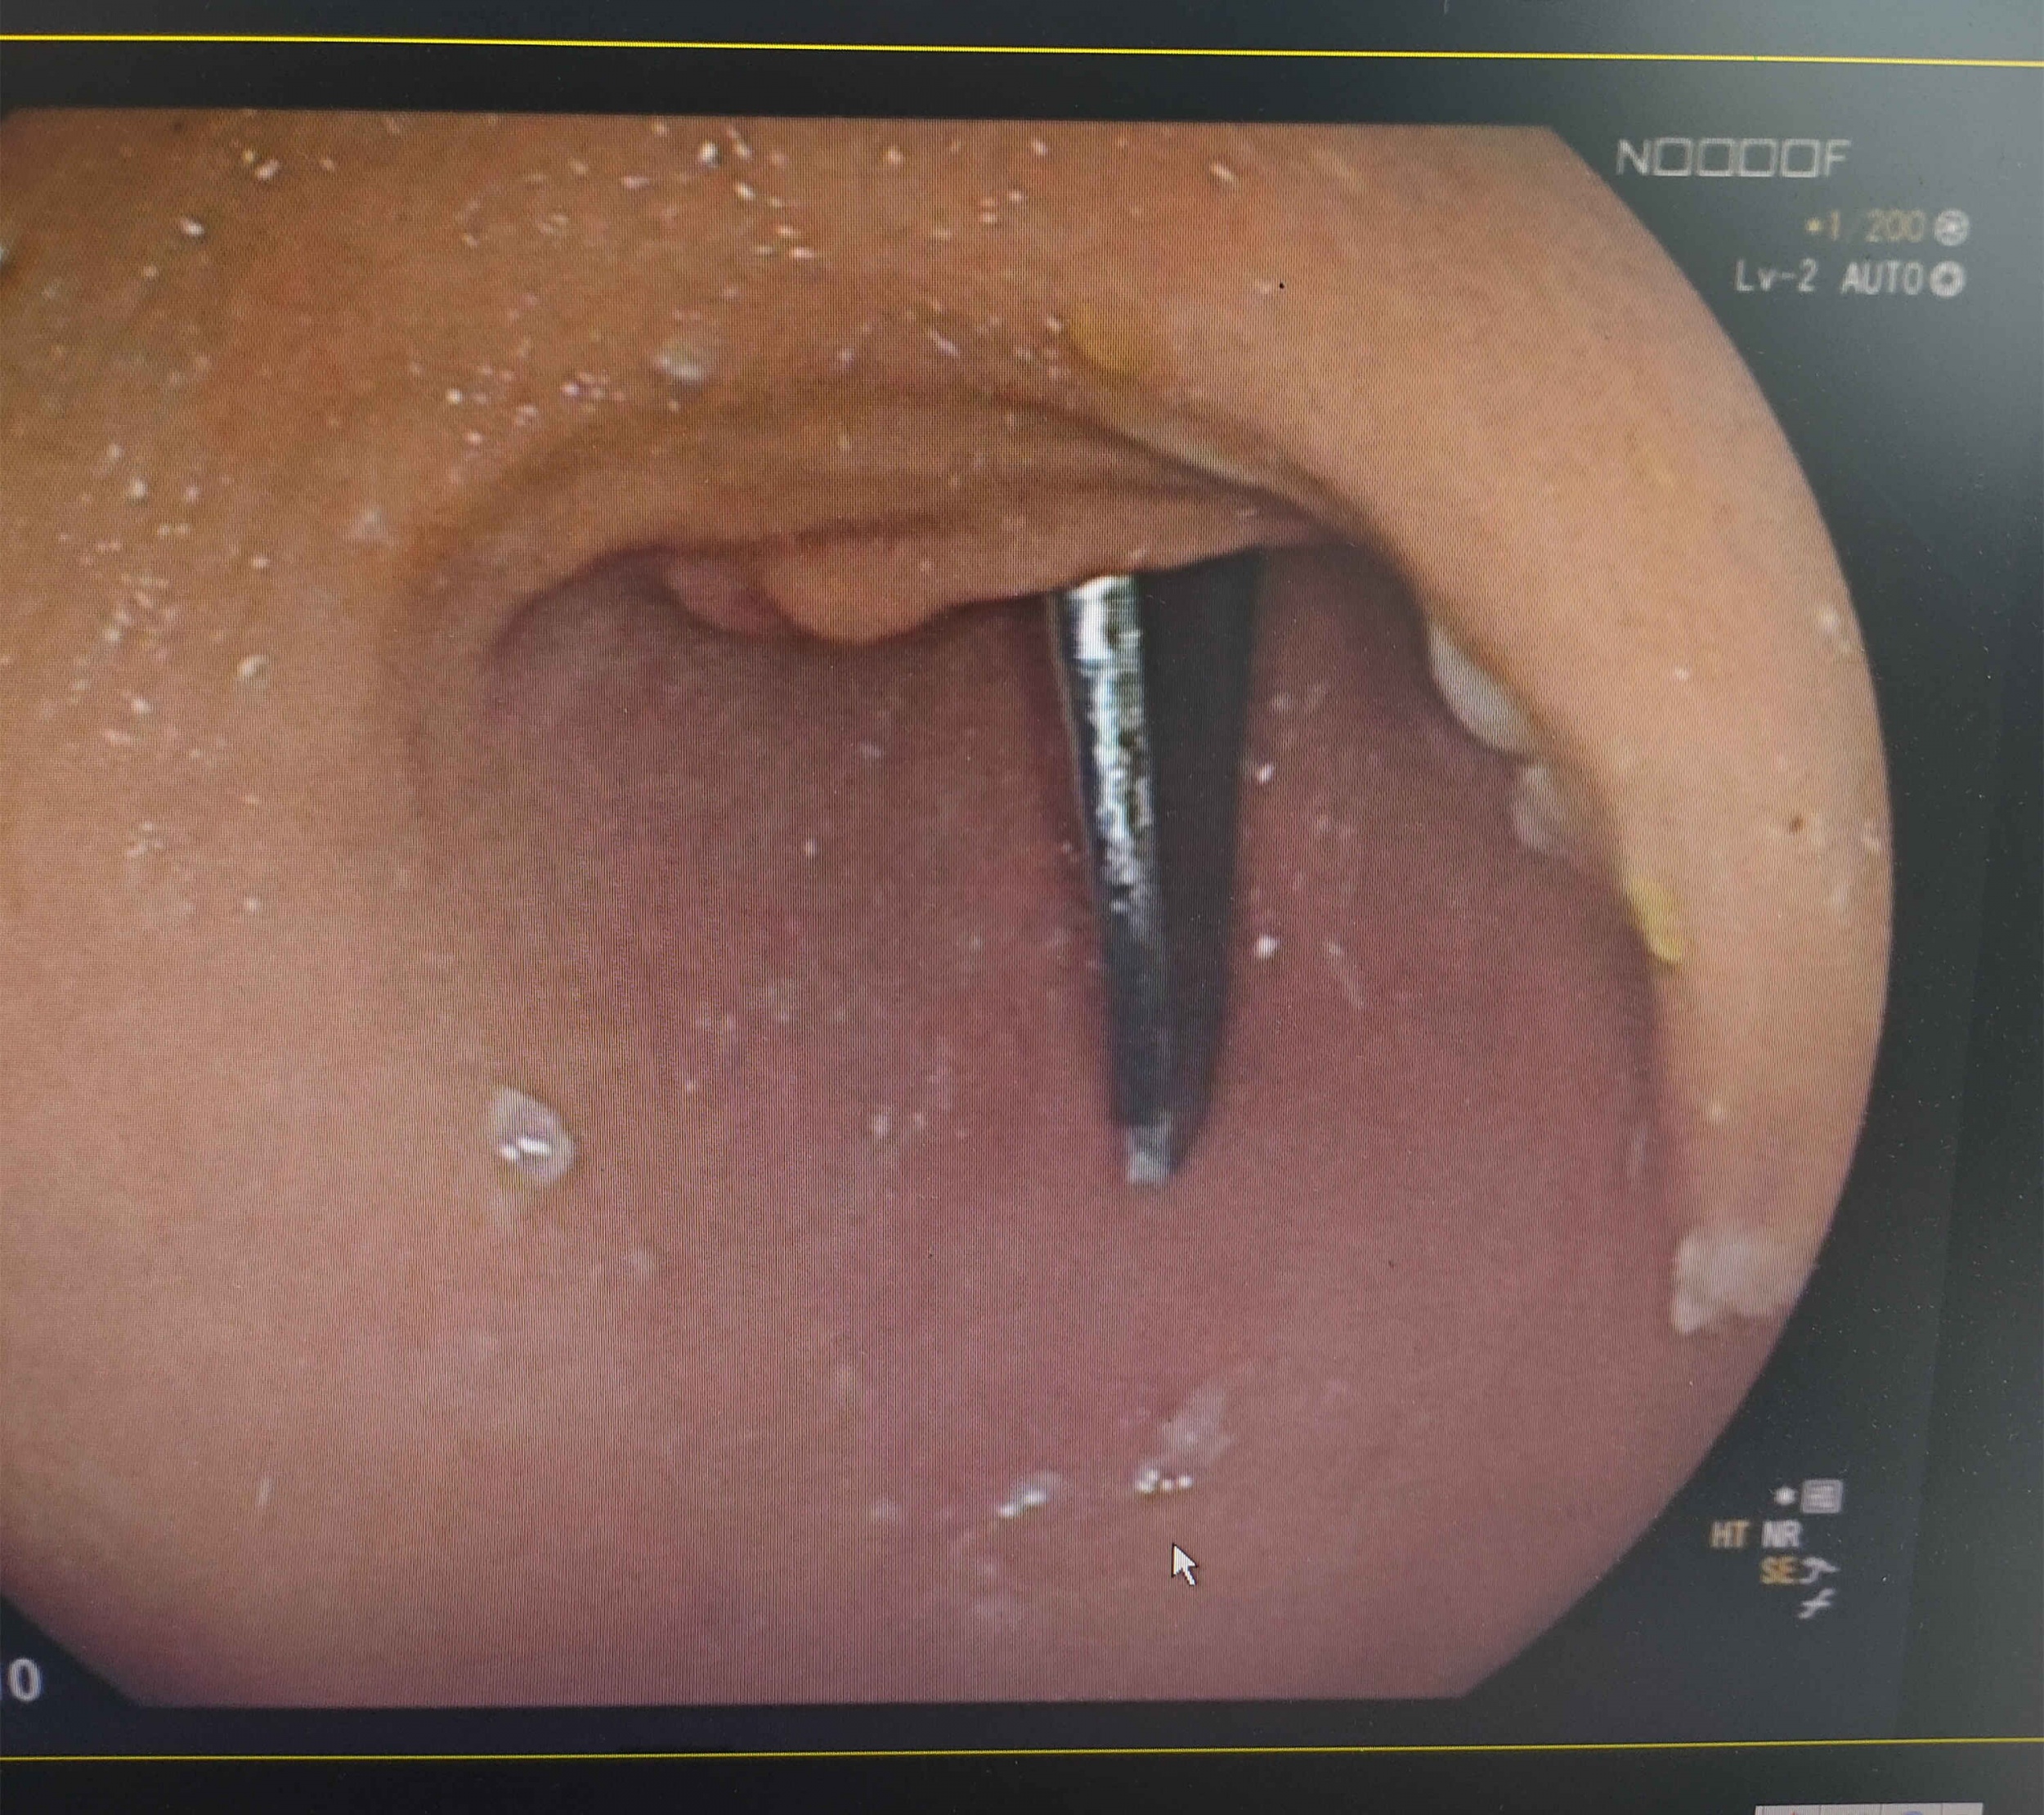

患者全身麻醉就绪后,在王智慧主任的指导下,消化内科团队行胃镜异物取出术,胃镜检查发现异物“剪刀”的一半在胃窦,另一半已经插进十二指肠,情况非常紧急,一旦全部掉进十二指肠,对取出手术带来巨大的困难,也极易造成十二指肠穿孔。

消化内科团队立即用异物钳把“剪刀”异物拉出十二指肠,放到胃体里,但由于“剪刀”异物过长、过重,且金属材料,表面光滑,异物钳力度完全不够,根本无法夹取,消化内科团队更换使用勒除器,并避免“剪刀”锋利的一端伤到患者食管和吞咽部,随后经过胃贲门部循食管腔退出胃镜到咽喉部。经过咽喉部生理弯曲时又遇到难点,长而坚硬且锋利的金属剪刀异物通过咽部极其困难,在众人齐心协力下,这把“剪刀”艰难的通过患者咽喉部从口腔取出。术后第二天,患者经观察后无任何不适,顺利出院。